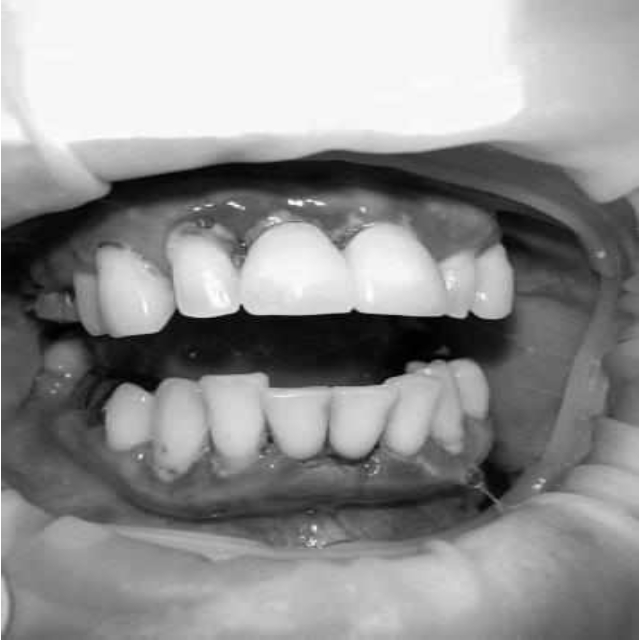

За пародонтологическим лечением обратилась женщина 61 года с жалобами на неприятный запах из полости рта, кровоточивость десен при чистке зубов, подвижность зубов, несостоятельность ортопедических конструкций.

Ранее у пародонтолога не наблюдалась. При осмотре выявлены: неудовлетворительная индивидуальная гигиена полости рта, пародонтальные карманы до 7 мм, обильная кровоточивость и гноетечение из пародонтальных карманов, подвижность зубов 4.2, 4.1, 3.1, 3.2 II степени, обильные над- и поддесневые зубные отложения (рис. 1). На ортопантомограме отмечается резорбция костной ткани до ½ длины корня, очаги остеопороза (рис. 2). Пациенту был поставлен диагноз хронический генерализованный пародонтит тяжелой степени тяжести. При осмотре была составлена пародонтограмма с использованием компьютерного зондирования (рис. 3).

Рис. 1. Внешний вид

Рис. 2. Ортопантомограмма исходной ситуации пациента состояния полости рта

Через 6 месяцев при осмотре выявлен удовлетворительный уровень индивидуальной гигиены, отсутствие участков кровоточивости и гноетечения (рис. 4), пародонтальные карманы уменьшились в размерах (рис. 5). Пациент отмечает значительные улучшения. После стабилизации пародонтологического статуса пациент направлен для дальнейшего ортопедического лечения.

Рис. 4. Динамика результата через 6 месяцев